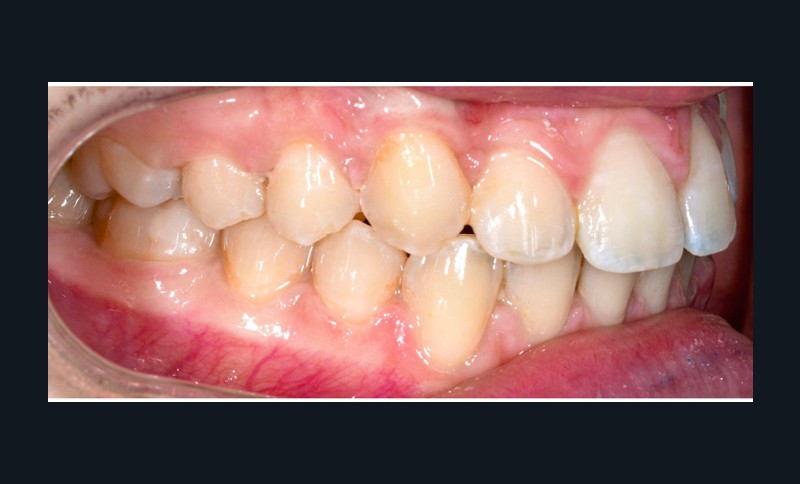

La patiente consulte à l’âge de 9 ans pour la malposition de ses incisives latérales maxillaires. Elle présente une occlusion de Classe I bilatérale sur un schéma normodivergent avec une dysharmonie dento-maxillaire en denture mixte. À l’arcade maxillaire, elle présente une endoalvéolie avec rotations mésiopalatines de 16 et 26.

Sur la radiographie panoramique, on observe une transposition des canines maxillaires en place d’incisives latérales, au contact des racines de 11 et 21.